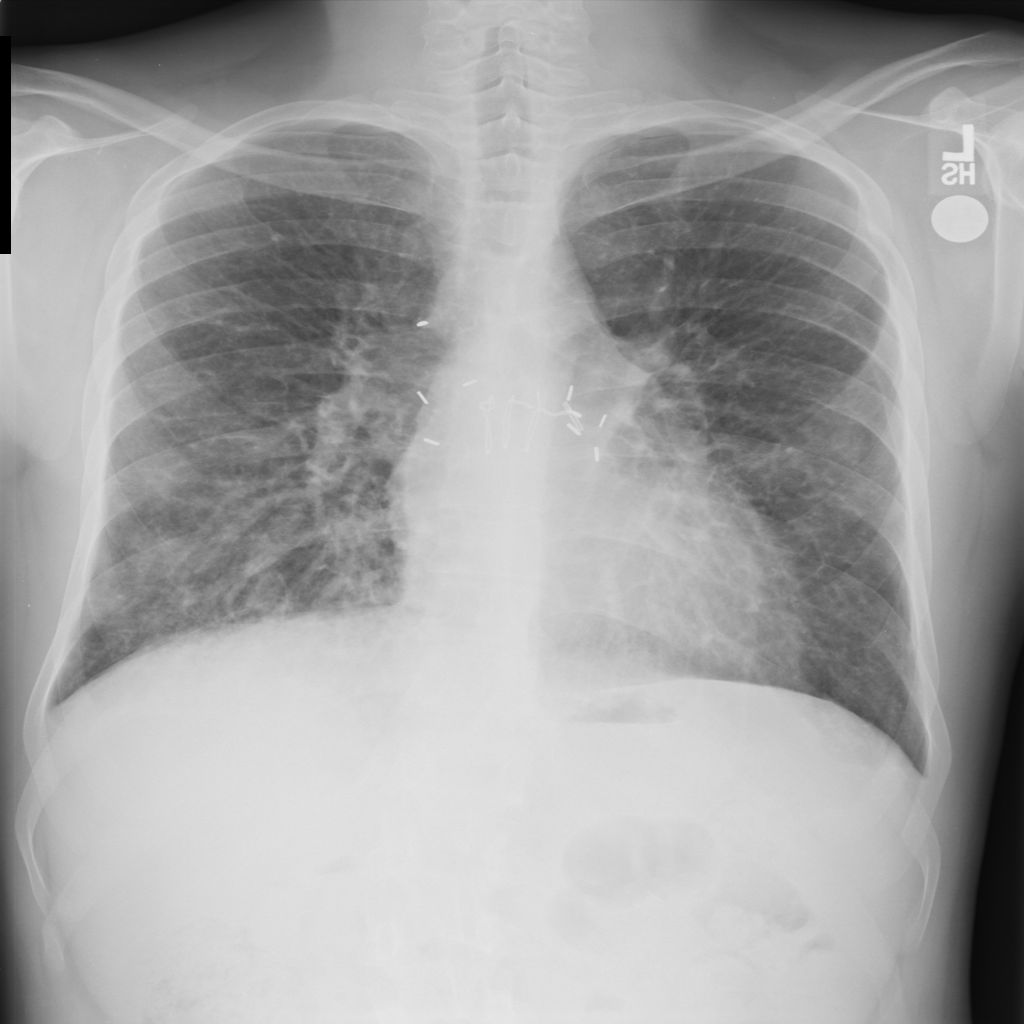

PAT-C0E5 · IMG-015Pneumonia

PAT-C0E5 · IMG-015

AP